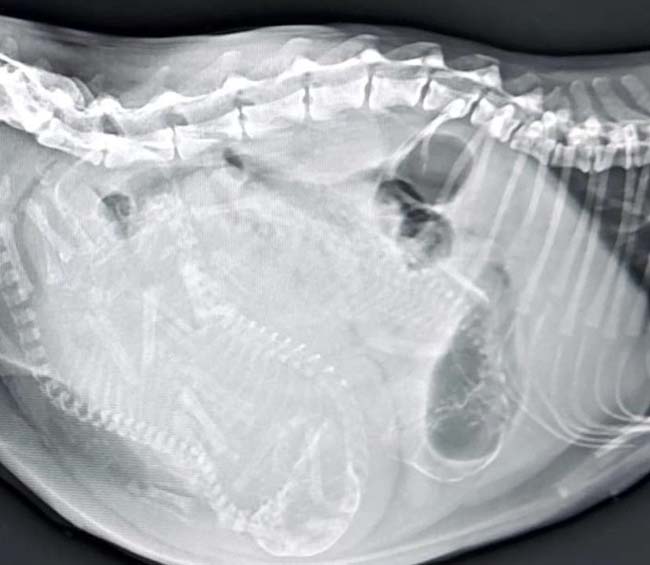

Zonguldak’ta 1 yaşındaki tekir cinsi kedi doğum yapamama nedeniyle kent merkezinde ki özel veteriner kliniğe getirildi. Veteriner hekim Gökmen Koç tarafından muayene edilen kedinin rahiminden yavruların sıkıştığı tespit edildi. Ardından sezaryenle ameliyatla alınan anne kedinin rahiminde sıkışan 3 yavru çıkartıldı. Ancak yavruların sezaryenle çıkartılması nedeniyle bu kez de anne kedi yavruları kabul etmedi. Hayvan sahipleri 6 gün boyunca yavruları anne kediye yaklaştırarak emzirmesini sağladı. 6 günün sonunda anne kedi yavrularını kabul etmesiyle problem çözüldü.

“Pazar sabahı kedimden akıntı geldi. Dışarı da kuyruğunu görüyoruz ama çok fazla ıkınıyor ağrısı acısı var. Doğumunu gerçekleştirmiyor. Yapılan tetkik ve ultrasonda kedimizin doğuramadığını ve kanala sıkıştığını tespit ettik. O yüzden ameliyat kararı verdik. O ilk sıkışan yavru gerçekten çok büyüktü. Kesinlikle kanaldan geçecek ebatlarda değildi. Rahminden çıkardık yavruları. Kızanın etkisi ile dışarıda hangi kedilerle çiftleşti bilinmiyor. Cüsseli bir erkek kesiyle çiftleşmiş haddinden büyüktü yavrular. Ardından da kapattık. İlk 5 gün anne kedi sezaryenle doğum yapıldığı için anne kedi yavrularını kabul etmedi. Hasta sahiplerini yavruları tutarsak anneye getirdi. 2 saatte bir böyle beslemeler yaptı. Annenin altında sıcaklığını korudu. Yeri geldi yavruların üzerlerini sürttürerek sıcaklıklarını anneye geçirtti. Şu anda 6’ıncı günün sonunda çok şükür anne yavrularını kabul etti ve beslemeye başladı. Annelik içgüdüsünü kazanmış hale geldi. Şu anda problem yok” dedi.